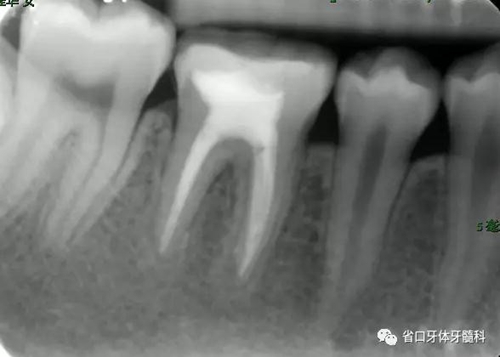

圖4 根管治療術(shù)后17個(gè)月:根分叉和根尖低密度影基本消失

2.本病例為牙髓組織來(lái)源引起齦緣、根分叉至根尖周區(qū)域貫通性的牙周組織損傷,在本病例的治療中,主要針對(duì)牙髓疾患行根管治療,牙周治療僅在初次治療時(shí)行牙周的簡(jiǎn)單處理,結(jié)果表明:完善的根管治療即獲得了良好的牙髓炎癥控制與牙周組織的愈合。

3.治療體會(huì):對(duì)于牙髓牙周聯(lián)合病變的患牙,病因的判斷對(duì)預(yù)后至關(guān)重要。本病例46齲源性的牙髓感染為首發(fā)因素,牙周組織破壞為繼發(fā)損害(圖10 左:Primary Endodontic Lesions with Secondary Periodontal Involvement),有學(xué)者稱之為牙髓牙周聯(lián)合病變,預(yù)后相對(duì)較好;牙周感染繼發(fā)牙髓病變(圖10 中:Primary Periodontal Lesions with Secondary Endodontic Involvement)則稱為牙周牙髓聯(lián)合病變和真性牙周牙髓聯(lián)合病變(圖10 右:True Combined Lesions )預(yù)后相對(duì)差一些。此外,患者的年齡也會(huì)對(duì)預(yù)后產(chǎn)生較大的影響,年齡越輕,其組織修復(fù)與愈合能力越強(qiáng)。